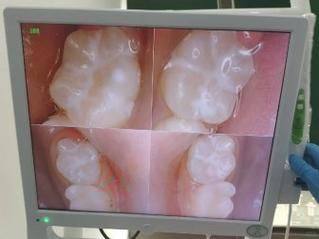

1. 精细诊断:使用Ⅲ类射线装置,能够更正确地检测口腔内部情况,为后续的治疗提供可靠依据。